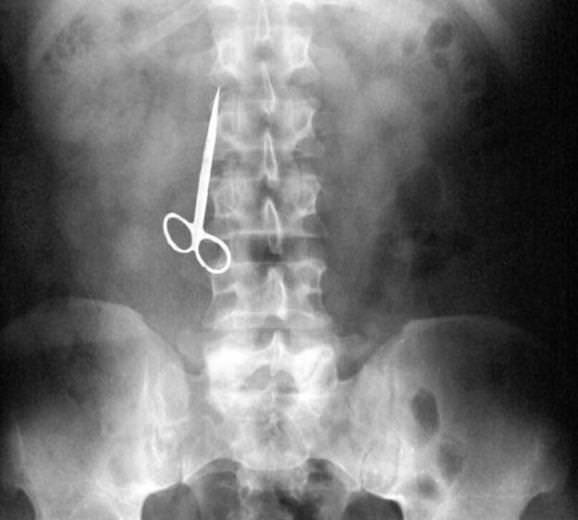

Röntgen filmlerinden "akıl almaz şeyler

Hastane koridorlarına düşenler bilir… Doktora görün, tahlilleri yaptır, röntgenleri çektir falan filan derken sayılmadan ömür gider. Gelin ki bu sefer ilginç şeyler çıkmış ki görün ağzımız açık kaldı…